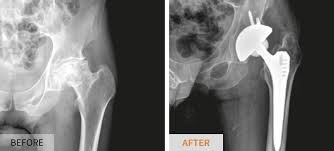

- 고관절 전치환술(Total Hip Arthroplasty, THA): 골관절염이나 류마티스 관절염, 골절 등에 널리 사용되는 방식으로, 관절 전체를 인공 관절로 교체합니다.

- 반치환술(Hemiarthroplasty): 대퇴골 두부 골절 등 특정 상황에 고관절 반만 인공으로 바꿔주는 방식입니다.